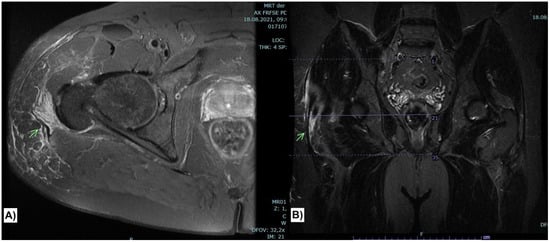

The main finding in the MRI was a localized collection of hematoma medial to the iliotibial band, between the iliotibial band and the greater trochanter (Figure 2). Compared to the left side, there was an increased distancing of the fascia lata or the iliotibial tract from the greater trochanter and a redundant, wavy cross-section of the fascia lata at the proximal thigh. Further, hematoma was also detected superficially, subcutaneously at the periphery of the iliotibial band and the gluteus maximus tendon. The insertion of the gluteus maximus muscle at the gluteal tuberosity of the femur was intact. Still, the insertion of the gluteus maximus tendon into the intermuscular septum was elevated and injured (Figure 2). Neither the gluteus medius nor the gluteus minimus tendons were injured. Also, the insertion of the quadratus femoris tendon and the insertion of the iliopsoas tendon at the lesser trochanter were intact. Some fluid was surrounding the tensor fasciae latae muscle. Otherwise, inconspicuous internal signals around the adductors and hip flexors were noticed.

Figure 2. Axial FRFSE PD sequence (A) showing collection of hematoma medial to the iliotibial band with disruption of the superficial insertion of the gluteus maximus muscle at the iliotibial band and intermuscular septum (Arrow). The injury is again demonstrated in coronal STIR sequence (B).